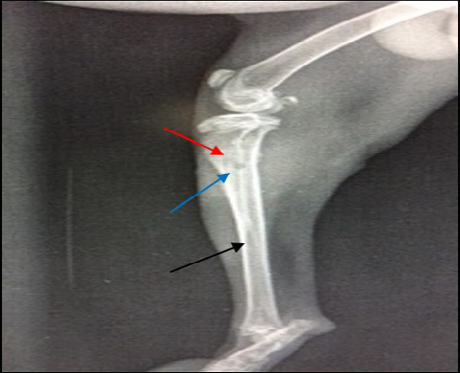

14 days post infection with MRSA, Area of bone lysis (Radiolucent spot) (→) surrounded by bone production (Radiopaque area) (→).Thickened cortex and severe periosteal reaction (→) (ML view)

A) 21 days post infection with MRSA shows Sever bone lysis (→), Thickened of cortex and sever periosteal reaction (→), Soft tissue suppuration (→) (ML view); B) Seqeustrum appeared (→) and abscesses (→) (AP view)